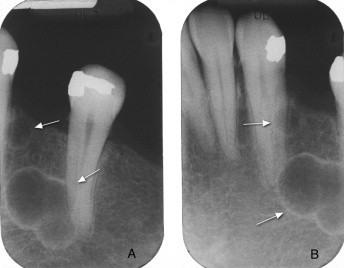

Is this a lateral periodontal cyst or radicular cyst?

lateral periodontal cyst